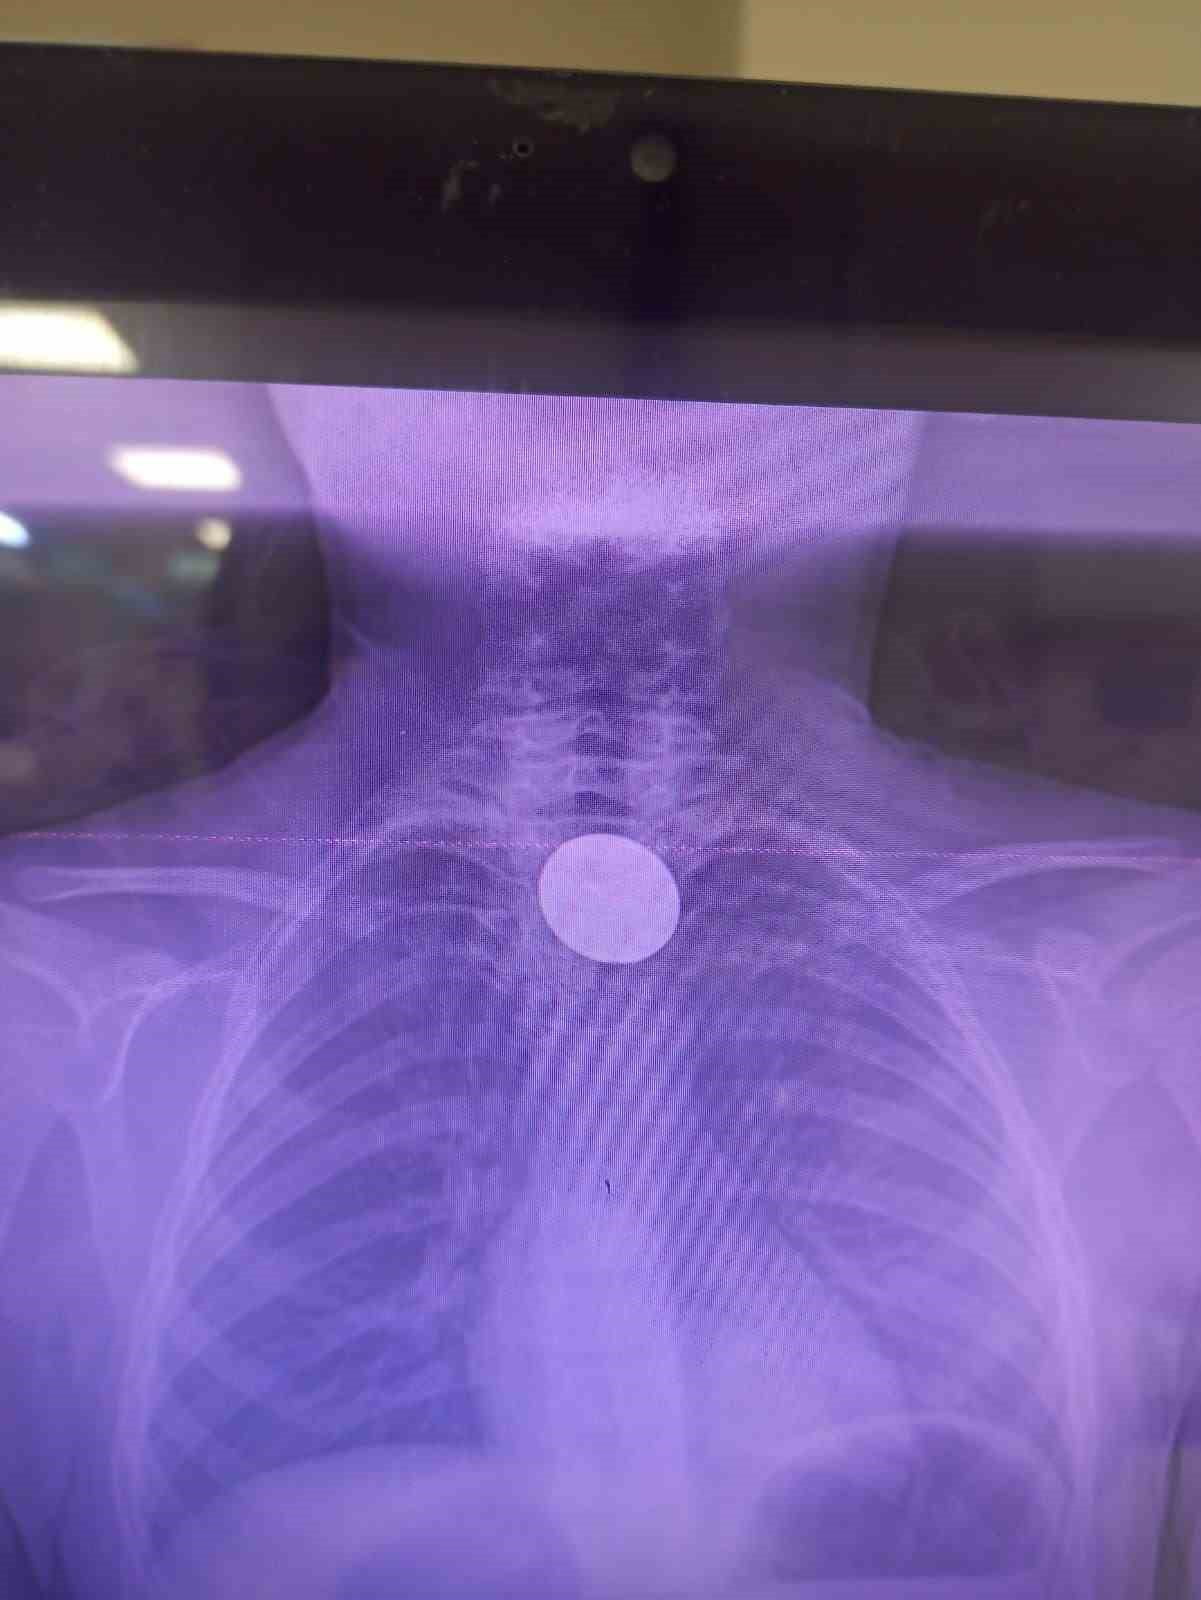

Yabancı cisim yutma şikayetiyle ailesi tarafından Siirt Eğitim ve Araştırma Hastanesine getirilen 8 yaşındaki Y.K., yapılan ilk değerlendirme ve görüntüleme tetkiklerinin ardından ilgili branşlarca operasyona alındı.

Y.K.'nın yemek borusuna kadar ilerlediği tespit edilen madeni 5 lira, gastroenteroloji uzmanı Dr. Yaren Dirik ve kulak burun boğaz hekimi Yasin Gökçınar tarafından yapılan müdahale ile çıkartıldı.